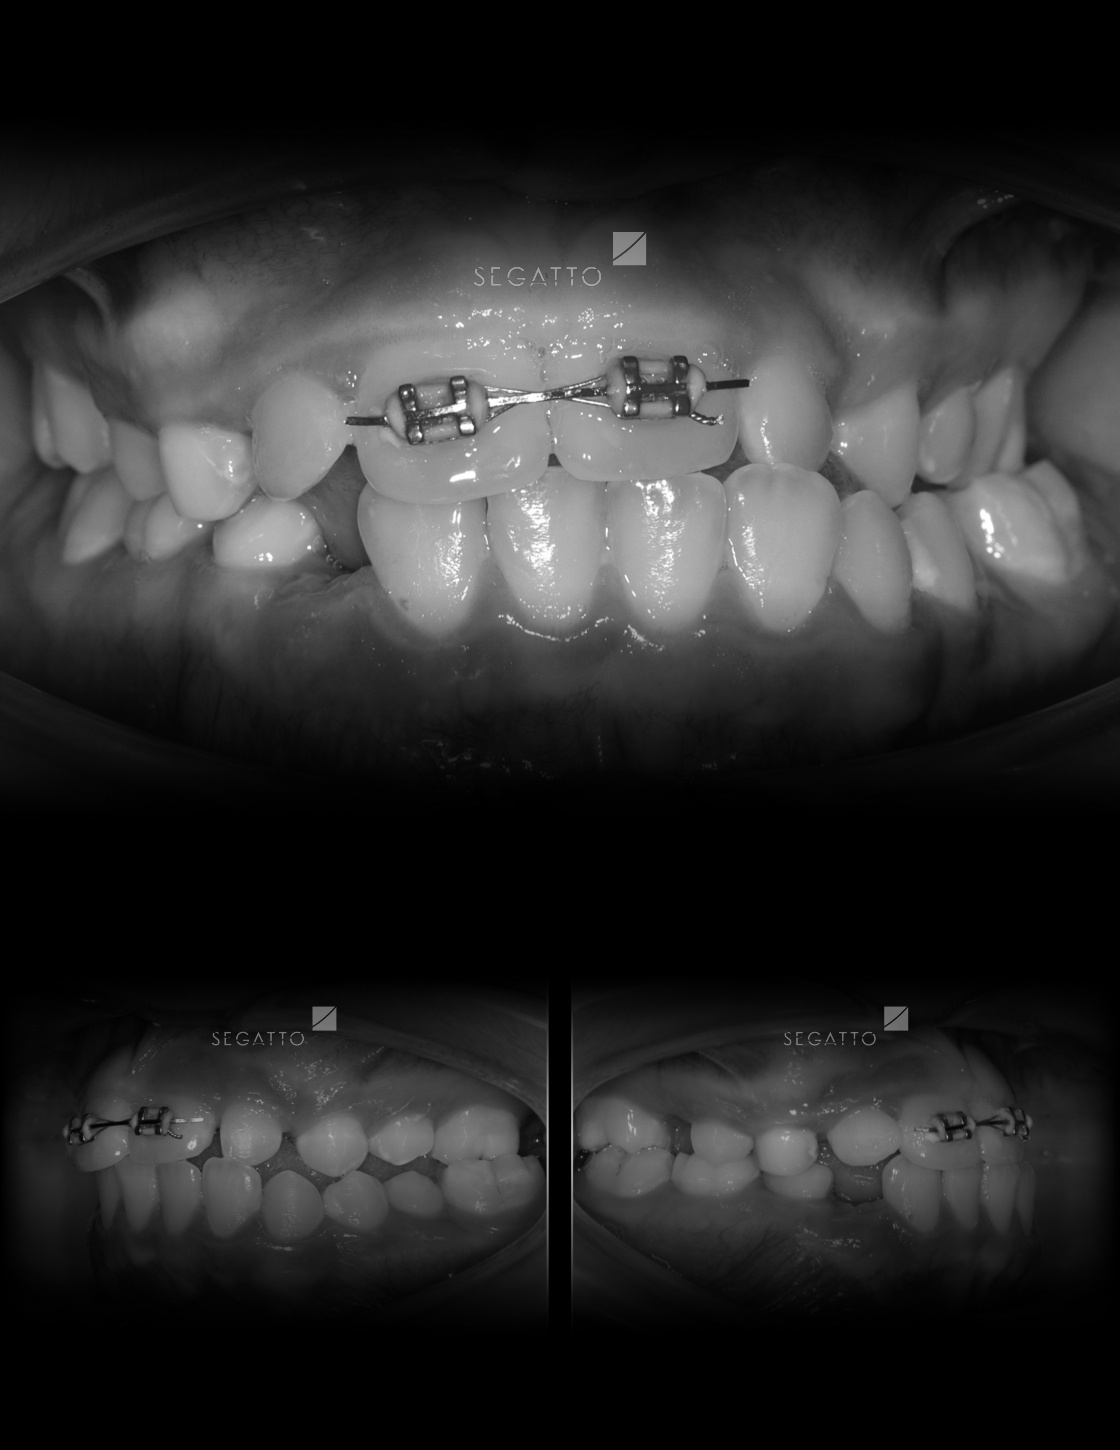

Orthodontics

Cases